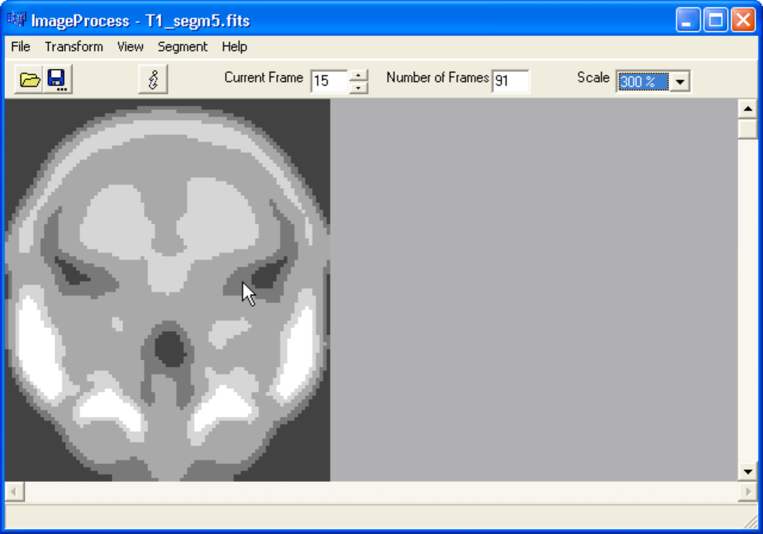

Refer to caption

Figure 4: Frame number 15 from an MRI brain image.

Consider T1, an aggregated representative brain, derived from MRI data. It is of dimensions 91×109×91911099191\times 109\times 91. See Figure 4. In the work described here as image format for the 3D or 4D image volumes we used the FITS, Flexible Image Transport System, format.